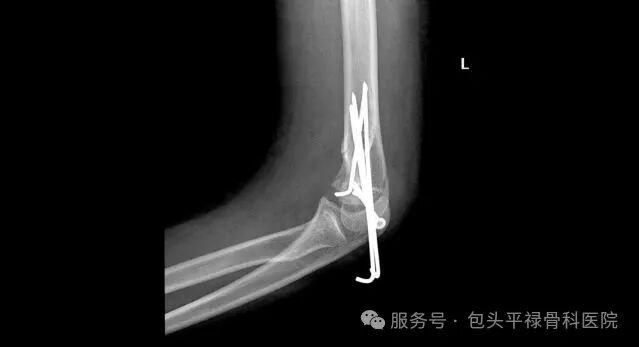

去除内固定后,骨骼上会留下多个“螺钉孔”(即钉道),这些钉道需由新生骨组织逐渐填满愈合,这个过程通常需要6-12周,在这个“空洞期”,骨骼的机械强度是下降的,过早或过度负重极易发生再骨折。